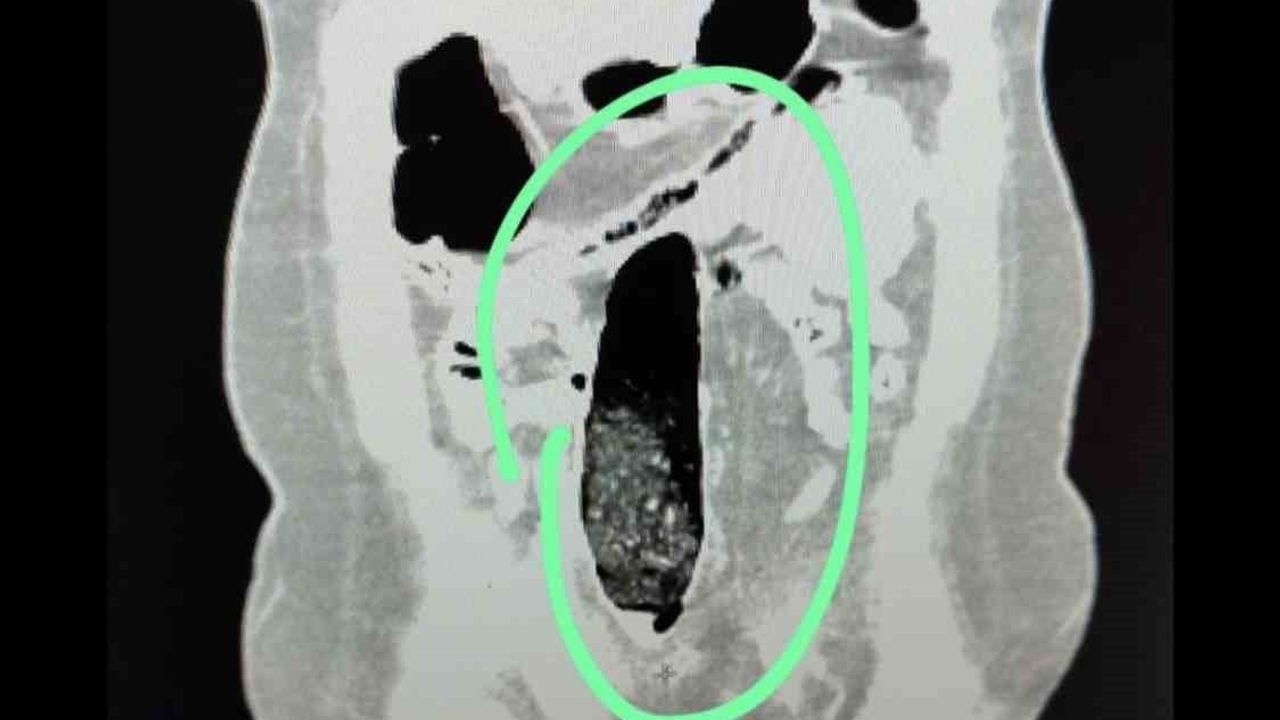

Yapılan kontrollerde şüpheli şahısların iç beden muayeneleri gerçekleştirilmiş; şahısların vücutlarının doğal boşlukları ve bağırsaklarında uyuşturucu madde bulunduğu belirlenmiştir. Tıbbi müdahale ile söz konusu maddelerin çıkarılması sağlanmıştır.

Tıbbi müdahale sonucu, F.V. isimli kadın şahıstan üç parça halinde toplam 397,78 gram metamfetamin ele geçirilmiş; S.İ. isimli erkek şahıstan ise 24 adet sentetik hap ile üç parça halinde toplam 167,68 gram metamfetamin elde edilmiştir.